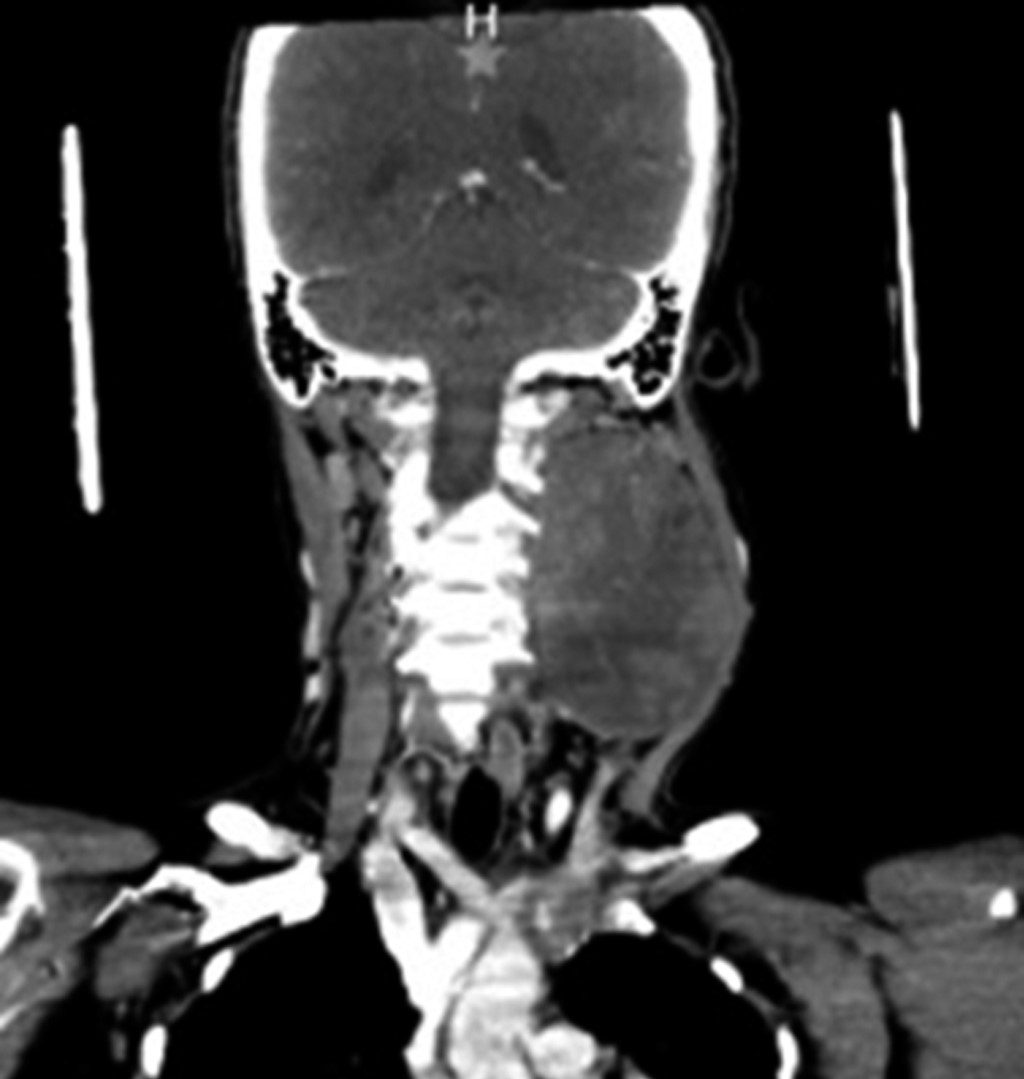

Sin datos de síndrome de respuesta inflamatoria sistémica, inestabilidad hemodinámica o compromiso cardiopulmonar, como complemento diagnóstico se solicita tomografía computarizada, la cual reporta gran masa redondeada de aspecto sólido de bordes regulares, bien delimitados, heterogénea de predominio hipodensa, con pequeñas zonas de menor densidad en su interior, sin identificar calcificaciones, con una densidad entre 24 y 37 UH y que posterior a la administración de medio de contraste intravenoso presenta una densidad entre 33 y 87 UH, localizado en nivel parafaríngeo izquierdo de 6.6 × 7.5 × 9.2 cm, lesión de espacio parafaríngeo izquierdo con sospecha de quiste branquial versus adenoma pleomorfo versus quiste branquial hemorrágico (Figuras 2, 3 y 4).

Figura 3